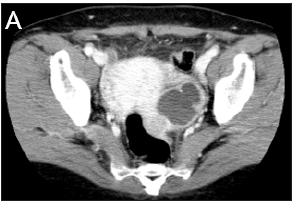

A 50-year-old postmenopausal woman, gravida 3, para 0, abortion 3, came to the emergency department because of abdominal pain and fever that occurred two days prior. Transvaginal ultrasound (TVUS) showed an ill-defined, multiseptated bilateral ovarian mass (right: 4.7*4.5cm, Lt: 3.6*3.9cm) in her pelvis. Abdominal-pelvic computed tomography (CT) also showed a multiloculated cystic mass in the bilateral ovary, r/o bilateral TOA. (Figure 1) She was given intravenous antibiotics for 14 days. Follow-up transvaginal ultrasound showed that bilateral ovarian mass had decreased in size but not completely resolved; then, it was decided to perform an operation. Open bilateral sapling-oophorectomy, appendectomy, partial omentectomy, adhesiolysis and bowel serosa 1’ repair was performed, and a Jackson-Pratt (JP) drain was placed in the posterior cul-de sac. Hysterectomy was considered but not performed as it was difficult to remove the posterior uterus, intestine and posterior cul-de sac due to severe adhesion. The operating time was 120 minutes, and the total blood loss was 100mL. The immediate postoperative period was uncomplicated.

Figure 1: Initial CT showing bilateral TOA.